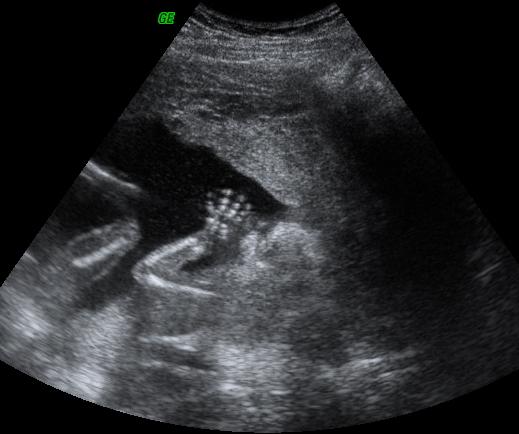

Munka után elmentem Szededre, ott aludtam, aztán reggel 7 h 20-ra mentem. 3-an voltunk, de így is csak 11 h-kor kezdték el!! Én voltam az első, 3 perc volt az egész. Az a doki csinálta, aki egy hete ultrahangozott. Nagyon profi volt, érződött rajta a sok éves rutin, de ettől függetlenül majd meghaltam az izgalomtól. A képernyőn olyan kicsinek tünt a szabad hely a baba mellett. Aztán már nem bírtam nézni, becsuktam a szemen. A szúrás picit fájt, meg az, hogy kicsit mozgatták bennem, de hamar megvolt. A szúrás helyén nagyítóval kell keresni,egy gombostűfejnyi vércsepp volt csak a kötésen. Délután 3h-kor már mehettünk haza, azzal, hogy sokat pihenjünk. A legrosszabb a 7 h 20-tól 11 h-ig való várakozás volt az egészben. Eredmény 3-4 hét múlva. Azt hiszem az izgalmasabb lesz. A társaimmal egy szobába kerültünk, jót beszélgettünk, elrepült az idő.

Képzeljétek kora reggel, ahogy várakoztunk tegnap, egy nővérke elkedzett vadászni a folyosón, és az egyik lányt, aki szintén amniora várt megkérte, menjen már be, mert most tesztelnek egy új UH-ot. És a doki megmondta 2 perc után, hogy fia lesz, eddig enm tudták a nemét. Mázlista Ő is! Ha két székkel arrébb ülök, lehet, már én is tudnám.